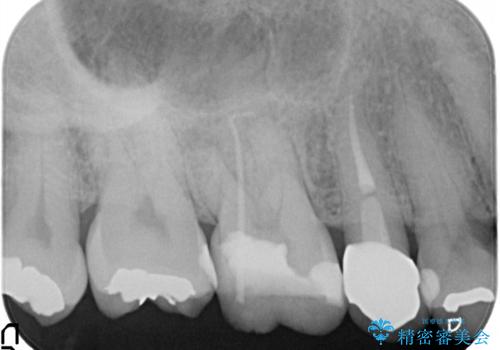

奥歯が痛い。根管治療

担当医 河口智英